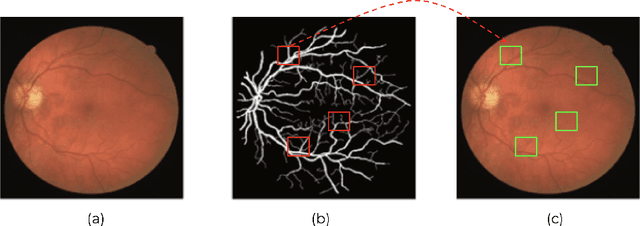

Abstract:This paper investigates the problem of domain adaptation for diabetic retinopathy (DR) grading. We learn invariant target-domain features by defining a novel self-supervised task based on retinal vessel image reconstructions, inspired by medical domain knowledge. Then, a benchmark of current state-of-the-art unsupervised domain adaptation methods on the DR problem is provided. It can be shown that our approach outperforms existing domain adaption strategies. Furthermore, when utilizing entire training data in the target domain, we are able to compete with several state-of-the-art approaches in final classification accuracy just by applying standard network architectures and using image-level labels.